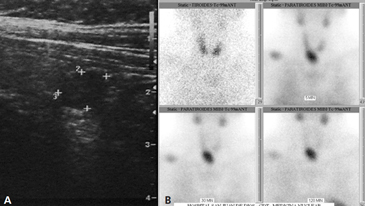

Los exámenes de laboratorio iniciales muestran calcemia 14,9 mg/dl (VN: 8,5-10,5 mg/dl), fosfemia 2,1 mg/dl (VN: 2,5-5 mg/dl), Parathormona (PTH) 1.862 pg/ml (VN: 11-67 pg/ml), 25-OH vitamina D 30 ng/ml (VN: 3,5-5), albúmina 4,5 mg/dl (VN: 3,5-5 mg/dl), Fosfatasa alcalina 910 U/L (VN), creatinina 1,7 mg/dl (VN: 0,6-1,3 mg/dl). Se realiza Ecografía cervical de alta resolución (Figura 2) que muestra tiroides normal y un nódulo hipogénico de 3 x 1,2 cm inferior derecho, compatible con un posible adenoma paratiroídeo, el que se confirma por un Cintigrama paratiroídeo con Tc99 SESTAMIBI, que muestra concentración anormal del trazador en región cervical, en relación a polo inferior del lóbulo tiroídeo derecho (Figura 2).

Figura 2. A) Ecografía cervical que muestra nódulo hipogénico de 3 por 1,2 cm inferior en el lóbulo tiroideo derecho, compatible con adenoma paratiroídeo. B) Cintigrama paratiroídeo con Tc99 SESTAMIBI.